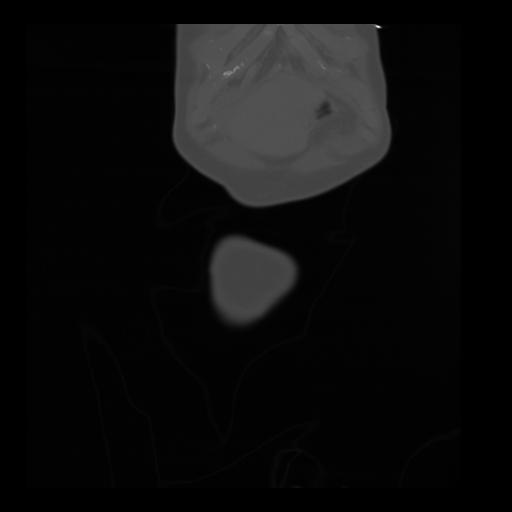

35 CUERPO,CE,Coronal,3.000,CUERPO,Coronal,